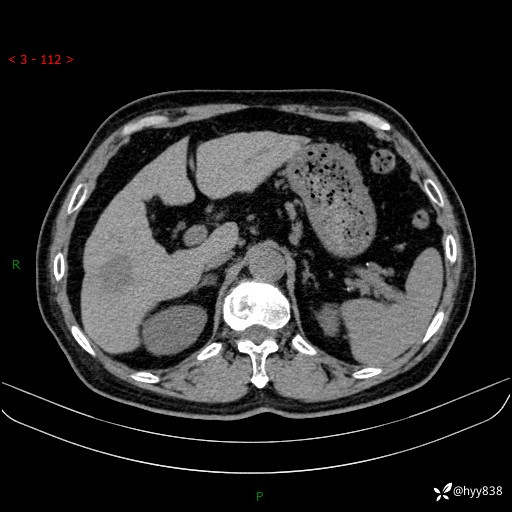

肝脏CT平扫